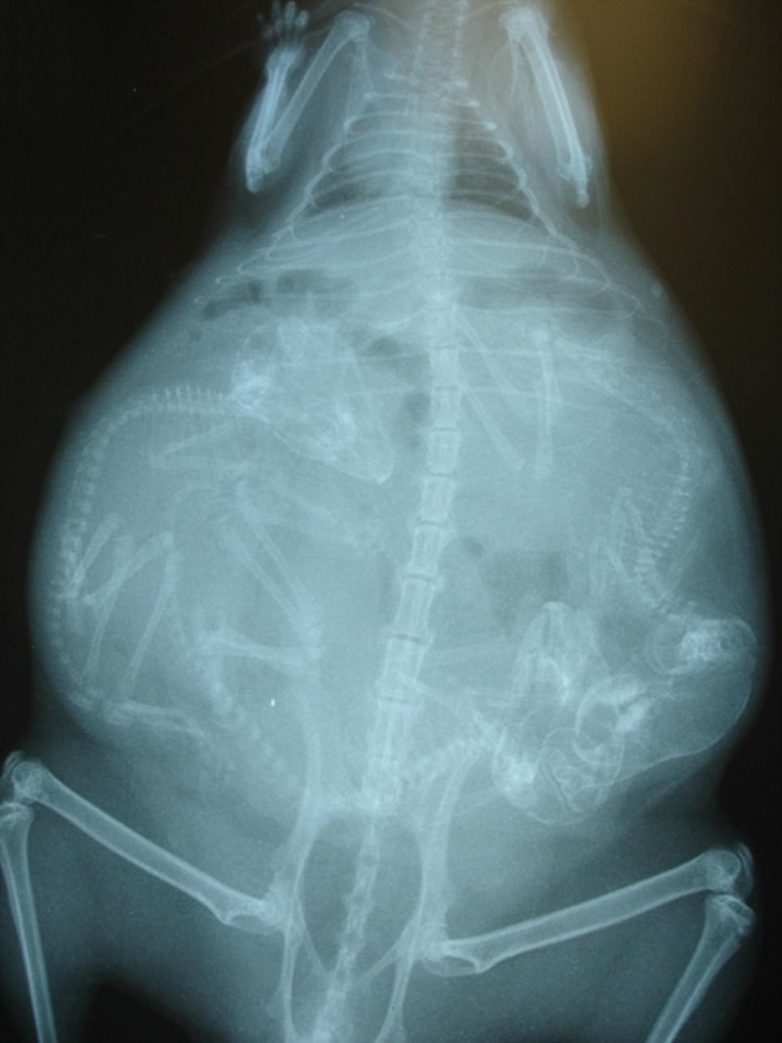

Беременность животных на рентген-снимках

Представляем вашему вниманию серию интересных рентгеновских снимков, на которых можно рассмотреть, как располагаются будущие детеныши енота, летучей мыши или, скажем, бородатой ящерицы в животах их мам.

Енот